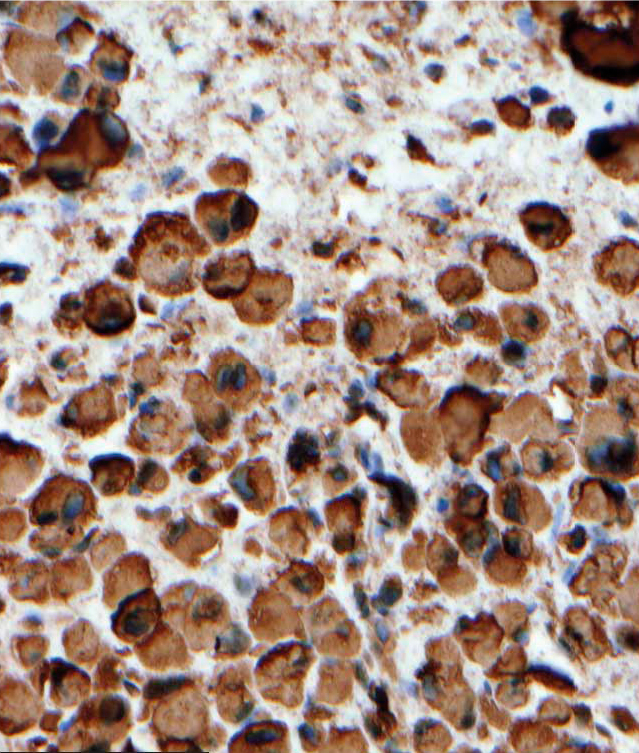

Why go through all the trouble setting up on-slide control tissue for every protocol? The reason is that tumor cells display abnormal staining patterns by nature (Figure 2), and therefore both high-expression and low-expression patterns should be expected. A qualitative IHC test should be able to correctly indicate if the marker is present, even in a low amount. The risk of a false positive is much lower than the risk of a false negative, since up to 90 percent of insufficient scores in an external quality scheme are due to a false negative result.13